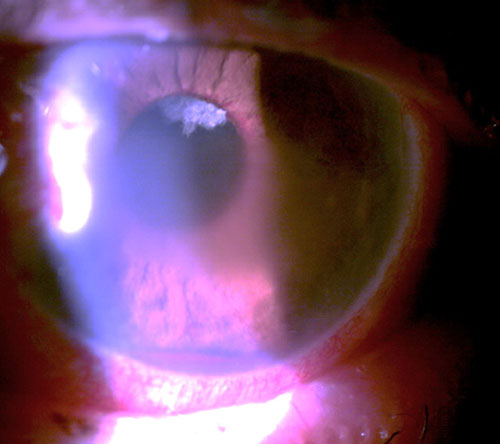

Case Challenge 14 – February 2020

Read more: Case Challenge 14 – February 2020An 82 year old man presented complaining of a moderately painful left eye of approximately 2-week duration. He was both diabetic and hypertensive. He was 20/25 OD and bare light perception OS. His intraocular pressure (IOP) was 23 mm Hg OD and 62 mm Hg OS. His left eye manifested central microcystic corneal edema,